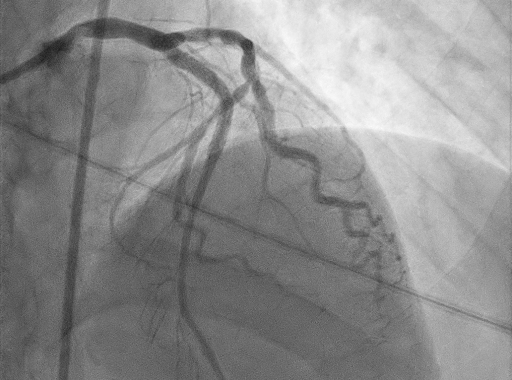

심장혈관 조영술은 요골동맥 또는 대퇴동맥에 가는 도관을 삽입하여 심장에 도달 시킨 뒤

관상동맥에 조영제를 주입하고, X-ray촬영으로 심장혈관을 실시간으로 관찰하는 검사입니다.

혈관질환의 진단 방법 중 가장 직관적인 검사방법으로 현재까지는 가장 정확도가 높습니다.

이 검사에 따라 약물치료, 관상동맥 중재술 등의 치료방침을 결정하게 됩니다.